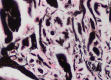

Isolated amyloidomas derived from insulin are extremely rare, and there is only one reported case to date of insulin-derived amyloidoma in the breast.We present the case of a 36-year-old woman reporting a lump in the right breast. It was clinically assessed as a probable fibroadenoma but was removed surgically given the size of the lesion. On histological analysis, the lesion had features consistent with amyloid. Further investigations showed the amyloid to be derived from insulin. The lump was removed in its entirety, and the patient made a full recovery.